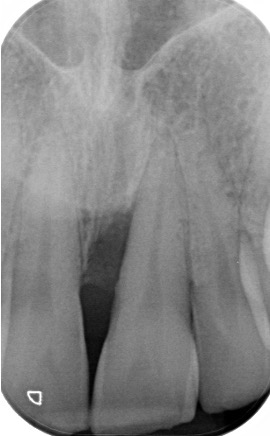

Regenerative periodontal surgery

Periodontal surgery is done in discrete areas of persistent disease that has not responded to non-surgical treatment. In this case a regenerative approach was done to “build-up” the bone. It can only be done in certain scenarios but can significantly improve the tooth’s prognosis